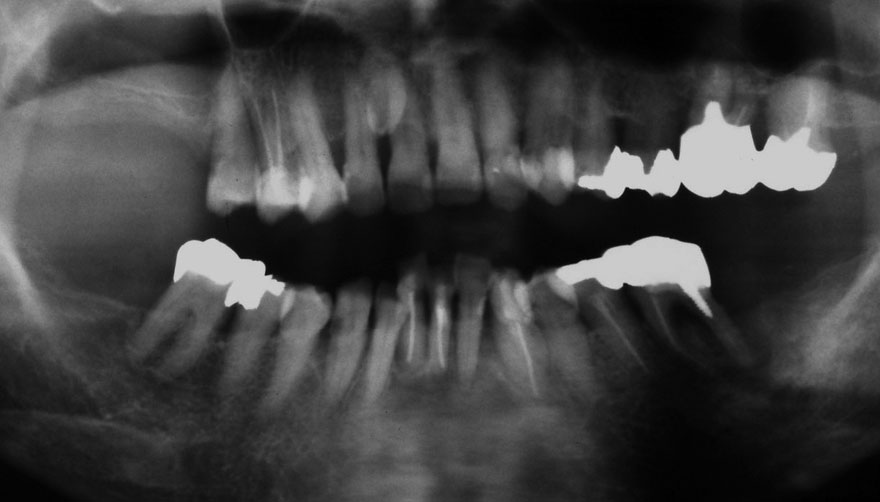

初診時 40歳 女性 平均歯槽骨喪失量:5.24mm

河田歯科医院

20年後 60歳

平均歯槽骨喪失量:5.79mm

21年間喪失量:-0.55mm

年間喪失速度:-0.027mm

(ケア頻度:1.23ヵ月ごと)